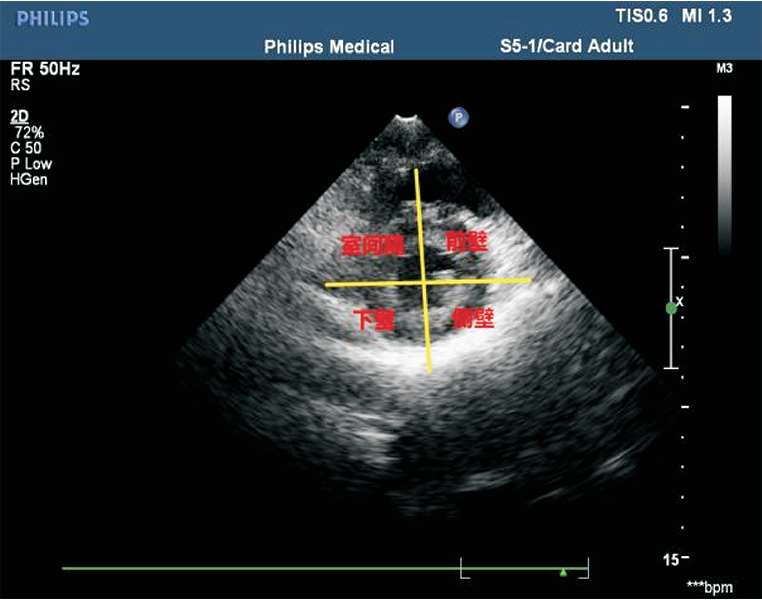

(7)常用的室壁分段方法为16段法。左心室长轴切面将左心室分为3等分:基底段、中间段及心尖段。基底段、中间段短轴切面分为6 等分:左心室前壁、左心室侧壁、左心室后壁、左心室下壁、后间隔及前间隔(见图1-38)。心尖段短轴切面分为4等分:左心室前壁、左心室侧壁、左心室下壁及室间隔(见图1-39)。

图1-38 基底段、中间段短轴切面分6等分